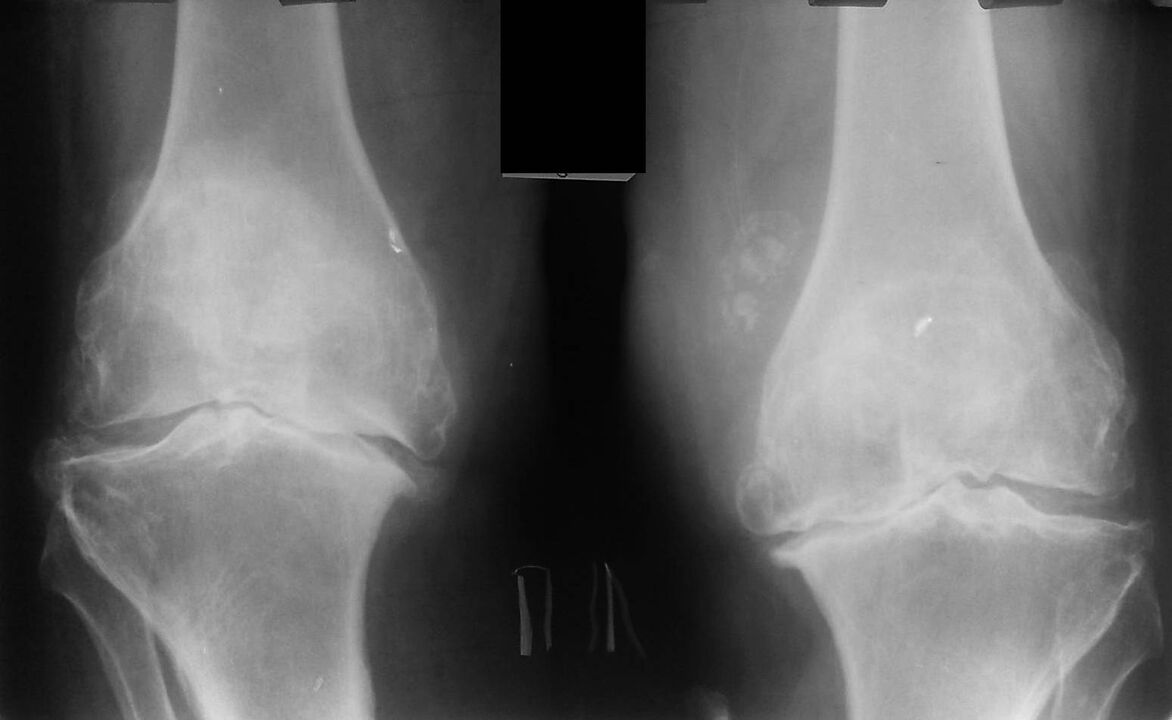

This diagnosis is made on the basis of patient complaints, examination data, palpation of the diseased ankle, and X-ray examination.

X-ray is a standard research method that allows you to confirm the diagnosis, determine the degree of pathological changes, monitor the dynamics of the process and also allows you to exclude other pathological processes (for example, tumors) in the tibia and femur. .

It should be noted that primary changes in knee joint structures on radiography may be absent. Next, the narrowing of the joint space and the compression of the subchondral area are determined. The articular ends of the femur and especially the tibia widen, the ends of the condyle become sharp.

Auxiliary methods of diagnosis are CT (computed tomography) and MRI (magnetic resonance imaging), which allow a more detailed study of pathological changes in bone structures and the identification of changes in soft tissues.